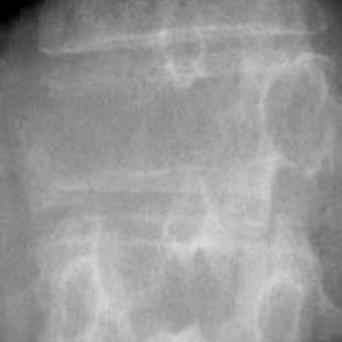

L’image

du jour

Illustration.